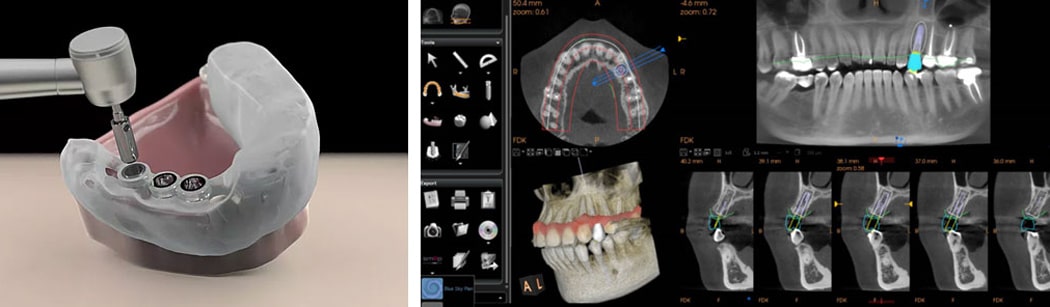

ایمپلنت دندان با پیشرفت فناوری به دو نوع اصلی سنتی و دیجیتال تقسیم شده است. ایمپلنت سنتی به مهارت دندانپزشک و قالب گیری حضوری وابسته